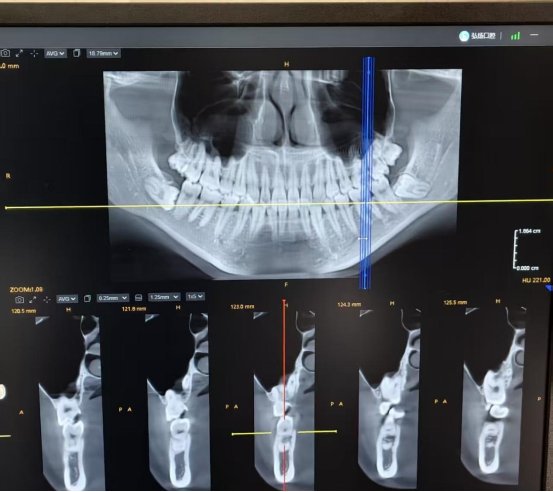

哪些智齿需要拔除?反复发炎的,通常建议拔掉;位置长不正、甚至倒着长的,一般也需要提前处理;如果智齿引起口腔溃疡或反复摩擦黏膜,同样建议拔除。

如果位置不正的智齿一直拖着不拔,有时会影响到旁边的第二磨牙,导致那颗好牙出现龋坏或松动。18岁到25岁是智齿萌出的常见年龄段,如果符合拔除指征,早点处理往往更省心。

智齿“不疼”不等于“安全”,位置不对可能是个隐患。如果智齿反复发炎或位置不正,尽早去医院请医生评估是否需要拔除,别等它影响到邻牙再处理。